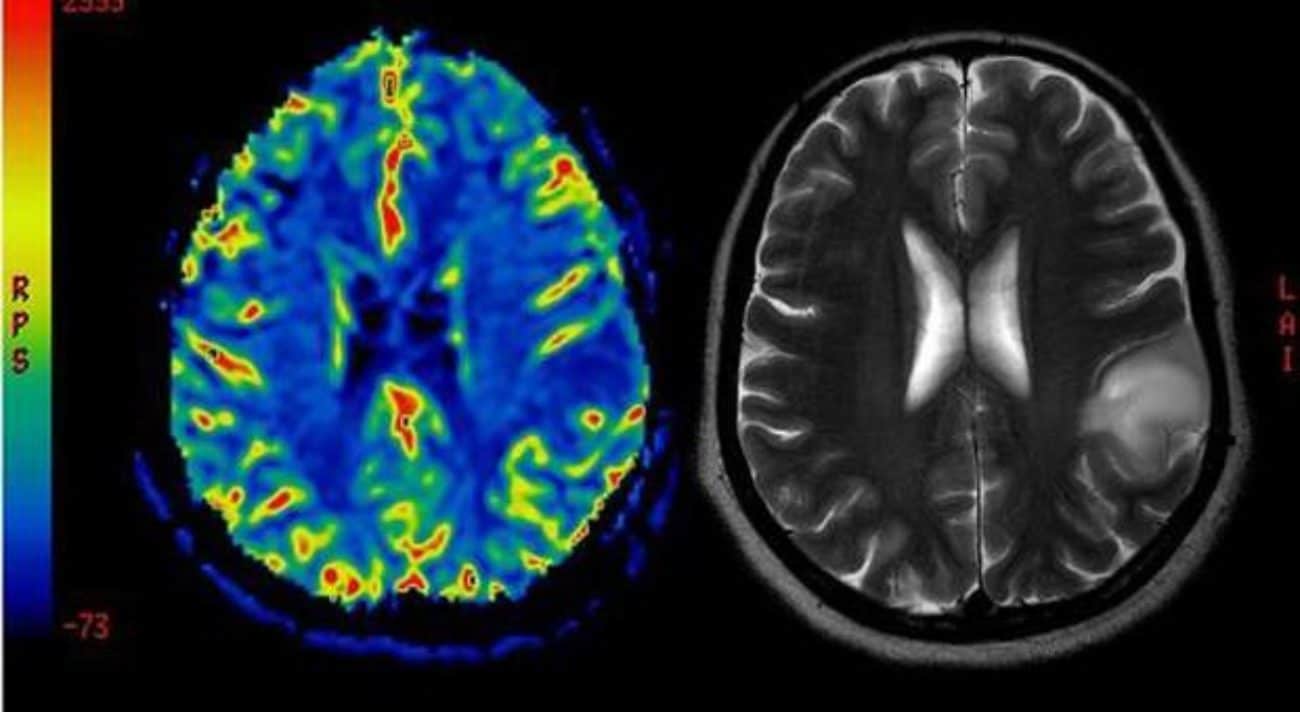

Una ricerca internazionale ha scoperto una proteina associata al morbo di Alzheimer in grado di contrastare i gliomi, tra i tumori celebrali più letali

In particolare questa proteina riuscirebbe a frenare l’aggressività dei gliomi, rari tumori maligni del cervello che possono trasformarsi nei più letali glioblastomi. Si tratta di tumori che sono particolarmente resistenti alla chemioterapia e ad altre terapie convenzionali, tanto da portare al decesso del paziente entro 15 mesi.

L’importante scoperta che la proteina tau può bloccare l’aggressività di questi tumori permetterà agli scienziati di trovare dei farmaci capaci di limitarne l’azione e quindi poter combattere il cancro. La ricerca, pubblicata sulla rivista Science Translational Medicine, ha quindi dimostrato che la proteina TAU si ritrova anche nelle cellule dei gliomi, dove reprimerebbe la loro capacità di creare nuovi vasi sanguigni, fondamentali per rifornirsi di nutrienti, favorendo la crescita e l’aggressività del tumore.